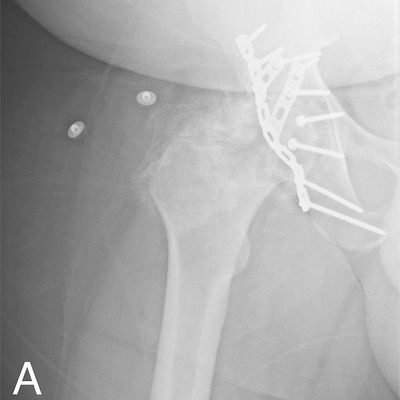

Click on an image below to view more info.